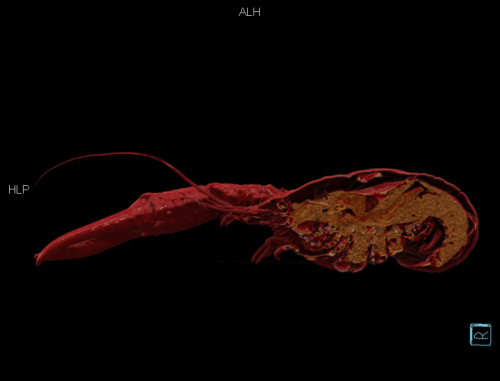

小龙虾侧位图 cVRT 重建(作者供图)

以下是小龙虾重建图像。

前后位,cVRT 重建(作者供图)